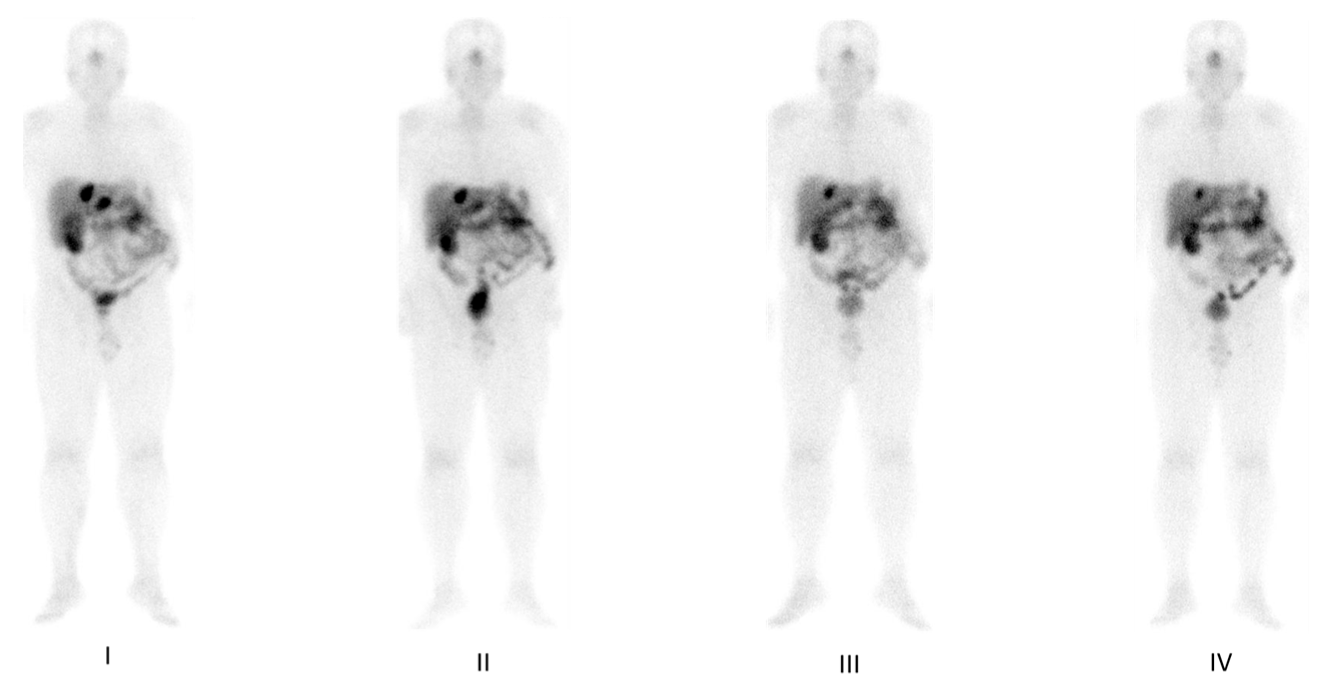

5. Imaging Analysis

8. Response to Therapy: Which Criteria?